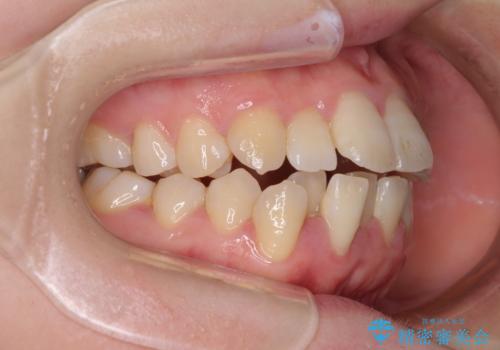

上下非接触で突出した前歯 ワイヤー装置による抜歯矯正

- 上下前歯の隙間と口元の出っ張った感じを気にして来院された患者様です。

上下の隙間は舌突出癖によるもので、またその癖により前歯が前方に出ている状態でした。

口元の出っ張りを改善するため、上下左右第一小臼歯4本を抜去し、ワイヤー装置にて矯正治療を行うこととしました。